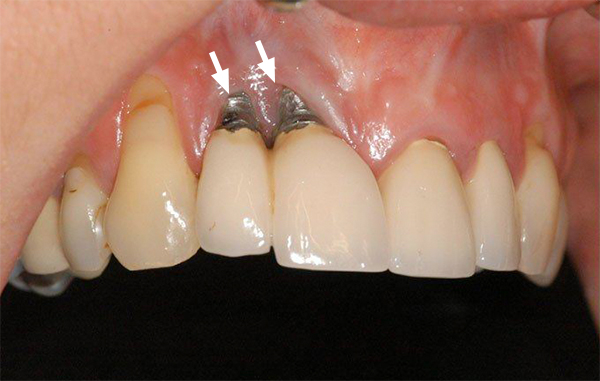

Hình ảnh giới thiệu về tình trạng răng implant bị đào thải

Trụ implant trồi lên

Một dấu hiệu cảnh báo nghiêm trọng khác là hiện tượng trụ implant trồi lên khỏi vị trí cấy ghép ban đầu. Khi bạn nhận thấy trụ implant có dấu hiệu di chuyển ra ngoài, điều này có thể chỉ ra rằng xương hàm xung quanh đang yếu đi, có thể do tình trạng tiêu xương hoặc áp lực không đều từ quá trình nhai. Trụ implant trồi lên không chỉ gây mất thẩm mỹ mà còn có thể dẫn đến các biến chứng khác, bao gồm viêm nhiễm. Việc phát hiện sớm hiện tượng này là cần thiết để có thể can thiệp kịp thời, tránh tình trạng nghiêm trọng hơn.

Hình ảnh trụ implant trồi lên